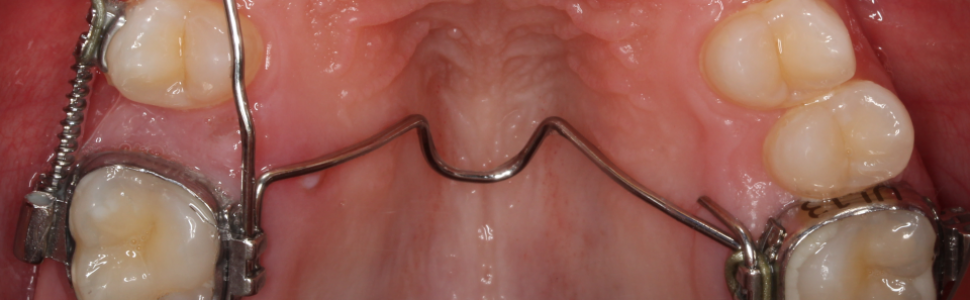

Przedwczesna utrata drugich zębów trzonowych mlecznych wskutek powikłań choroby próchnicowej jest często spotykanym problemem u dzieci. Istotnym następstwem jest wówczas mezjalizacja pierwszych zębów trzonowych stałych i spowodowane tym zamknięcie miejsca dla drugich zębów przedtrzonowych. Celem pracy jest zaprezentowanie metody odtworzenia całkowitego braku miejsca dla drugiego zęba przedtrzonowego w szczęce za pomocą stałych aparatów grubołukowych.

Early loss of second primary molars due to complications of caries is a common problem in children. An important problem is mesialization of the first permanent molars and the lack of space for second premolars. The aim of the article is to present a method of regaining the space for second premolar in maxilla using fixed orthodontic appliances.

Hasła indeksowe: GMD, łuk podniebienny, dystalizacja zębów trzonowych, leczenie bezekstrakcyjne

Key words: GMD, transpalatal arch, molar distalization, non-extraction treatment